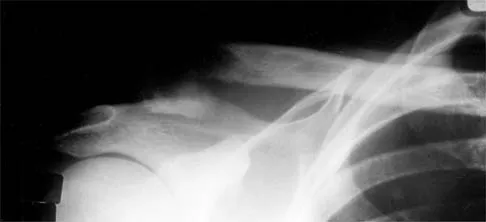

Question 97High Yield

Figure 11a shows the clinical photograph of a 46-year old woman who reports a 3-week history of pain and a "lump" at the base of her neck. She is otherwise in good health and denies any trauma. A 3-D reconstruction CT is shown in Figure 11b. What is the most likely diagnosis?